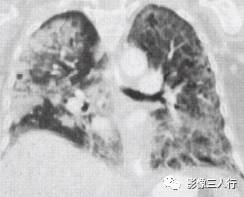

非典型肺炎的CT征象特点:分布不均匀、形态不同、大小不一的肺实变是本组 患者共同存在的基本CT表现。肺实变通常由于肺泡内充盈浆液性、渗出性或血性液 体、炎细胞或其他成分,导致肺实质弥漫性或局灶性密度增高。早期表现为边界不 清楚的0.5〜1.0cm的结节性高密度灶,随着病变的进展,融合成团块或斑片状阴 影,掩盖肺血管纹理。较大的实变影像内可见支气管分支的透亮影则为空气支气管征。见图9。